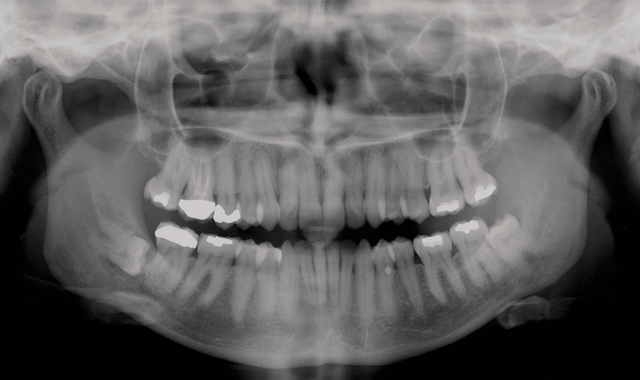

The patient was in the office in 2006 for a routine check-up and consented to a panoramic X-ray. The X-ray revealed no pathology associated with the #32 tooth. The patient was informed of the risk of cyst development associated with the impacted third molar, which would include the possibility of temporary or permanent damage to the inferior alveolar nerve.

Routine panoramic X-ray